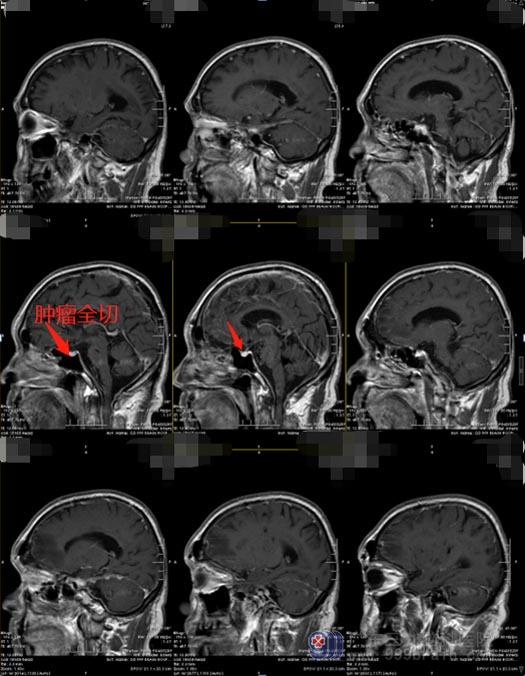

经眉弓锁孔入路切除鞍区附近及前颅窝底的病变,正好迎刃而解这一难题。该方法手术路径短,“锁孔”骨窗显露额底区域,通过解剖通道到达颅内病变部位,减少了脑组织的牵拉,优化视野,减少组织损伤;与开颅方法相比,不牺牲手术效率和安全性,可以到达大部分前颅底区域:鞍上、海绵窦外侧、近段侧裂、Willis环、额底和颞叶以及中脑腹侧,软组织损伤最小,减少了术后疼痛,恢复更快。手术只需要一个孔,也减少了术后瘢痕,可以保持术前的容貌外观,是一种安全、有效的微创手术方式。

黄爷爷和家人欣然接受了手术。充分的术前准备后,经过三个多小时的时间,手术顺利完成。手术后,黄爷爷未出现术后并发症,视力也得到了明显改善,两周后便满意出院了。